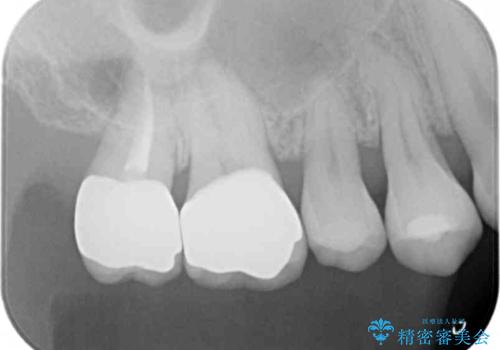

- 銀歯を白くしたいとのことで来院されました。

銀の詰め物を除去した後、その奥にある古い詰め物も除去し完全にむし歯を取り切ったことを確認してからセラミッククラウンを装着していきます。

- 右上67 仮歯+ジルコニアクラウン:11,000+110,000円 右上7/根管治療:保険 ファイバーコア:22,000円費用は治療当時の料金となります